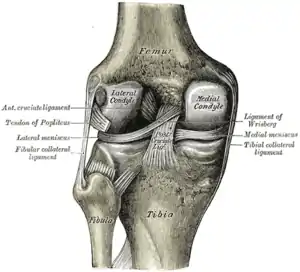

Intracapsular

The knee is stabilized by a pair of cruciate ligaments. These ligaments are both extrasynovial, intracapsular ligaments.[17] The anterior cruciate ligament (ACL) stretches from the lateral condyle of femur to the anterior intercondylar area.[13] The ACL is critically important because it prevents the tibia from being pushed too far anterior relative to the femur.[13] It is often torn during twisting or bending of the knee.[18] The posterior cruciate ligament (PCL) stretches from medial condyle of femur to the posterior intercondylar area. This ligament prevents posterior displacement of the tibia relative to the femur.[13] Injury to this ligament is uncommon but can occur as a direct result of forced trauma to the ligament.

The transverse ligament stretches from the lateral meniscus to the medial meniscus. It passes in front of the menisci. It is divided into several strips in 10% of cases.[10]:208 The two menisci are attached to each other anteriorly by the ligament.[19] The posterior (of Wrisberg) and anterior meniscofemoral ligaments (of Humphrey) stretch from the posterior horn of the lateral meniscus to the medial femoral condyle. They pass anterior and posterior to the posterior cruciate ligament respectively.[13][10]:208 The meniscotibial ligaments (or "coronary") stretches from inferior edges of the menisci to the periphery of the tibial plateaus.

Extracapsular

The patellar ligament connects the patella to the tuberosity of the tibia. It is also occasionally called the patellar tendon because there is no definite separation between the quadriceps tendon (which surrounds the patella) and the area connecting the patella to the tibia. [20] This very strong ligament helps give the patella its mechanical leverage [21] and also functions as a cap for the condyles of the femur. Laterally and medially to the patellar ligament the lateral and medial retinacula connect fibers from the vasti lateralis and medialis muscles to the tibia. Some fibers from the iliotibial tract radiate into the lateral retinaculum and the medial retinaculum receives some transverse fibers arising on the medial femoral epicondyle.[10]:206

The medial collateral ligament (MCL a.k.a. "tibial") stretches from the medial epicondyle of the femur to the medial tibial condyle. It is composed of three groups of fibers, one stretching between the two bones, and two fused with the medial meniscus. The MCL is partly covered by the pes anserinus and the tendon of the semimembranosus passes under it.[10]:206 It protects the medial side of the knee from being bent open by a stress applied to the lateral side of the knee (a valgus force).[10]:206

The lateral collateral ligament (LCL a.k.a. "fibular") stretches from the lateral epicondyle of the femur to the head of fibula. It is separate from both the joint capsule and the lateral meniscus.[10]:206 It protects the lateral side from an inside bending force (a varus force). The anterolateral ligament (ALL) is situated in front of the LCL.

Lastly, there are two ligaments on the dorsal side of the knee. The oblique popliteal ligament is a radiation of the tendon of the semimembranosus on the medial side, from where it is direct laterally and proximally. The arcuate popliteal ligament originates on the apex of the head of the fibula to stretch proximally, crosses the tendon of the popliteus muscle, and passes into the capsule.[10]:206